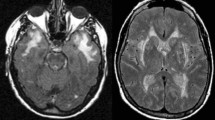

Although there were no known strokes in the family, she had a family history of dementia, with her father being diagnosed of ‘Alzheimer’s disease’ at age 55 and dying at age 63. Her father’s identical twin had no strokes or dementia but had not had an MRI scan prior to death also at age 55, and his sister had a diagnosis of ‘probable dementia ’ (Fig. 24.2).

MR imaging of her brain showed confluent T2 hyperintensities in the white matter involving the anterior temporal poles and external capsules. (Fig. 24.2, 2-2, 2-3) A lumbar puncture performed at the time of her first admission was normal and negative for oligoclonal bands. Genetic screening for NOTCH3 mutations revealed a p.Arg151Cys mutation in Exon 4.

She underwent neuropsychological assessment and was found to have impaired attention, information processing skills and some executive function difficulties—features commonly seen in small vessel disease-related cognitive impairment. An MRI of her brain showed widespread hyperintensities in the periventricular white matter and central pons. (Fig. 24.3, 3-2, 3-3).

(inset 3-1) Pedigree of clinical case 3, showing a clear family history of early-onset strokes in II.1, II.2 and II.3. Insets 3-2 and 3-3 MR T2-weighted imaging showing confluent white matter hyperintensities not dissimilar to those seen in sporadic cerebral small vessel disease, or CADASIL. (Copyright Hugh Markus)

On MR imaging of the brain, she was found to have marked white matter hyperintensities and lacunar infarcts, (Fig. 24.4, 4-2, 4-3) and an aneurysm of the left internal carotid artery in the region of the carotid ophthalmic artery. There was also evidence of microbleeds on gradient echo MRI. (Fig. 24.4, 4-4, 4-5).

(inset 4-1). Pedigree of Clinical Case 4 illustrating a wide variability of phenotypes among mutation carriers. While the proband had a paediatric onset of strokes, II.2 had MRI features of SVD in the fourth decade of life, but no strokes, and II.3 was born without a kidney—a feature previously reported in COL4A1-associated SVD cases. (4-2, 4-3) T2-weighted FLAIR MR images of II.2 showing confluent white matter hyperintensities and silent lacunar infarcts. Insets 4-4 and 4-5: Gradient-echo MR images of II.2 showing haemosiderin deposits and microbleeds. (Copyright Hugh Markus)